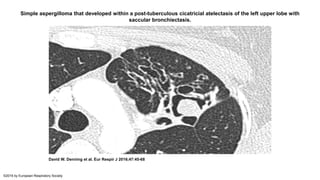

• On radiographic imaging, an aspergilloma appears as a round, well-

formed mass inside a pre-existing cavity, and it is often termed a 'fungus

ball' or 'mycetoma' by radiologists.

Simple aspergilloma that developed within a post-tuberculous cicatricial atelectasis of the left upper lobe with

saccular bronchiectasis.

David W. Denning et al. Eur Respir J 2016;47:45-68

©2016 by European Respiratory Society

Single (simple) pulmonaryaspergilloma • Single (simple) pulmonary aspergilloma is a single fungal ball in a single pulmonary cavity. • There is no progression over months of observation and very few, if any pulmonary or systemic symptoms and serological or microbiological evidence implicating Aspergillus spp. • Patients with a simple aspergilloma usually present with an incidental finding on radiographic imaging that was performed for another reason or for investigation of hemoptysis. Patients typically have no symptoms or have symptoms that are difficult to distinguish from those of their underlying lung disease. The most common symptom is cough. Hemoptysis may occur, including massive hemoptysis in a small subset of patients. Systemic symptoms (eg, fever, weight loss) do not occur in this form of CPA. • On radiographic imaging, an aspergilloma appears as a round, well- formed mass inside a pre-existing cavity, and it is often termed a 'fungus ball' or 'mycetoma' by radiologists.

Simple aspergilloma thatdeveloped within a post-tuberculous cicatricial atelectasis of the left upper lobe with saccular bronchiectasis. David W. Denning et al. Eur Respir J 2016;47:45-68 ©2016 by European Respiratory Society